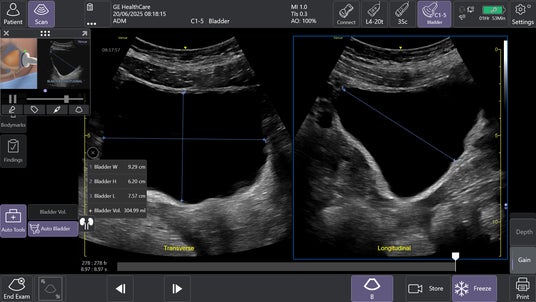

2.AIツールAuto Bladder Volume(オートブラッダーボリューム)で膀胱評価を効率化

AIを用いて開発されたAuto Bladder Volumeは、膀胱の容積を半自動で計測するツールです。横断像および縦断像の2方向の画像から、AIが自動的に膀胱形状を認識し容積を算出するため、再現性の高い評価が可能になります。

救急外来や集中治療室、手術後、病棟など様々な場面での活用が想定され、侵襲的な処置を行う事なく迅速かつ効率的な膀胱容積評価が可能となります。

Auto Bladder Volumeにより2断面から半自動的に膀胱容積を計算